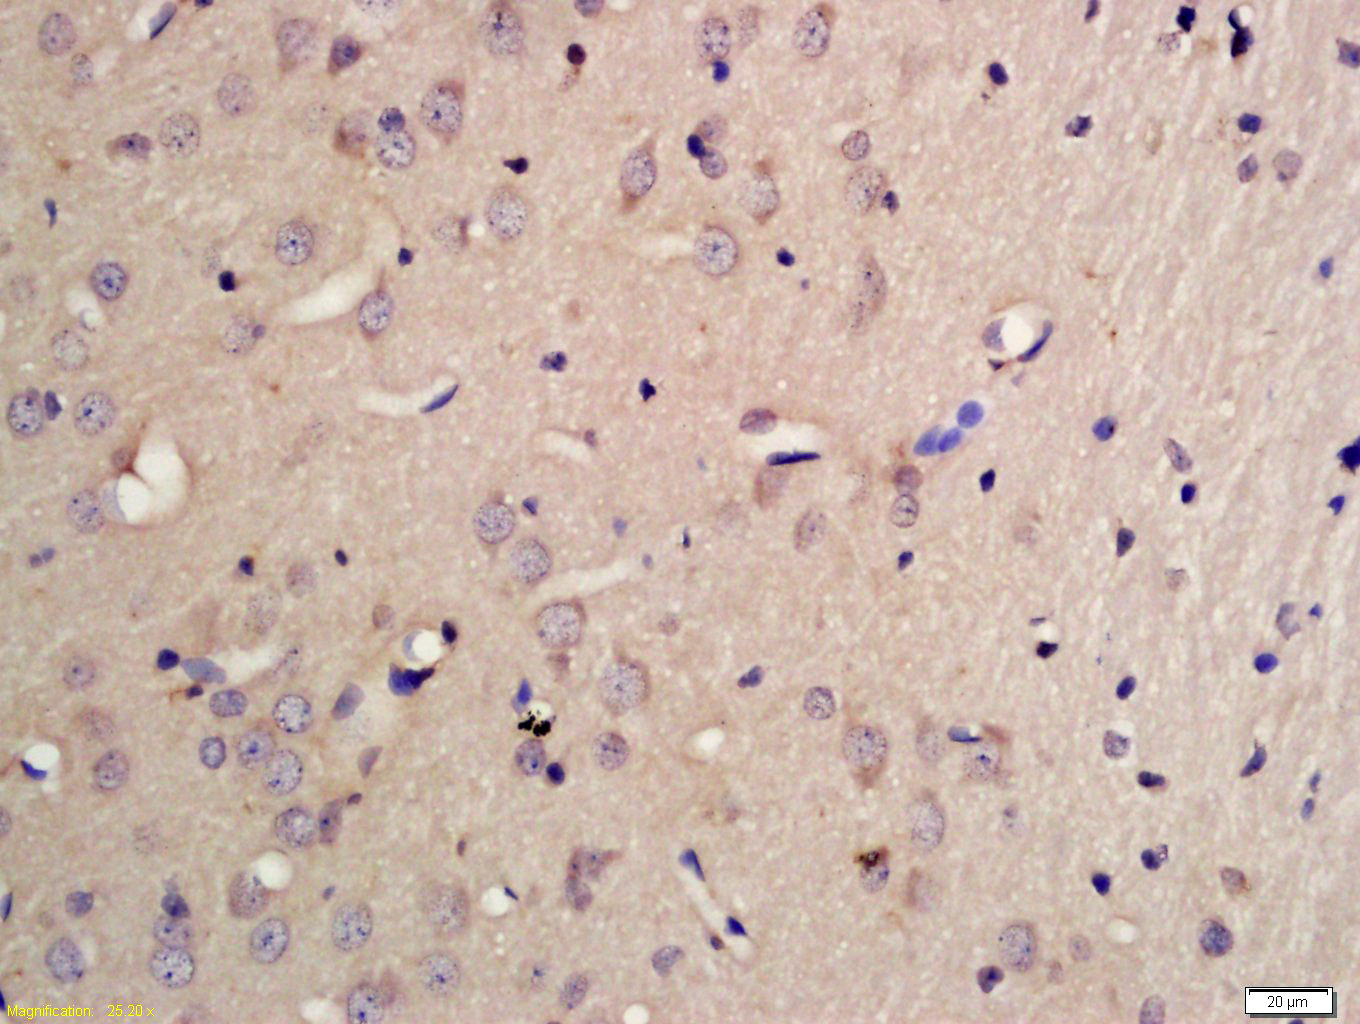

Tissue/cell: rat brain tissue; 4% Paraformaldehyde-fixed and paraffin-embedded; Antigen retrieval: citrate buffer ( 0.01M, pH 6.0 ), Boiling bathing for 15min; Block endogenous peroxidase by 3% Hydrogen peroxide for 30min; Blocking buffer (normal goat serum,C-0005) at 37℃ for 20 min; Incubation: Anti-PCDHB10 Polyclonal Antibody, Unconjugated(bs-13725R) 1:200, overnight at 4°C, followed by conjugation to the secondary antibody(SP-0023) and DAB(C-0010) staining